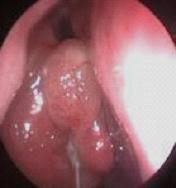

鼻息肉是赘生于鼻腔或鼻窦粘膜上突起的肿块。好发于鼻腔的外侧壁及鼻顶部。鼻息肉并非真性肿瘤,往往是变...[详情]